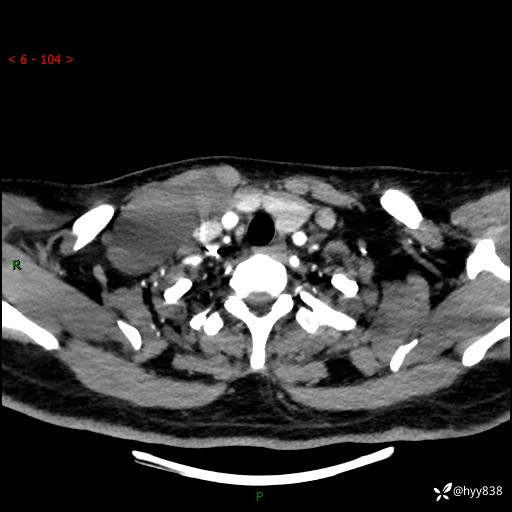

辅助检查:CT

颈部CT平扫

增强动脉期+静脉期